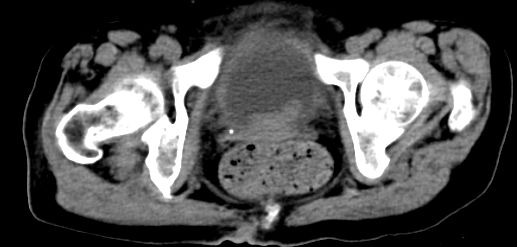

标题: CT10133:F、74岁,反复血尿10天。 [打印本页]

标题: CT10133:F、74岁,反复血尿10天。

考虑膀胱癌可能性大伴双侧输尿管下端扩张.

膀胱后壁见不规则致密影,我们遇到这样的病人都再做一次俯卧位扫描;排出膀胱内凝血块。

1.膀胱后壁见不规则致密影,占位?膀胱内凝血块?建议俯卧位扫描、膀胱镜检查.

2.双侧输尿管下段扩张.

膀胱三角区不规整软组织改变,双侧输尿管扩张,所以占位性病变肯定首先考虑,建议改变体位扫描除外游离血块影,但老年人出血原因一定要查明。

1.膀胱后壁见不规则致密影,随体位改变,为膀胱内凝血块;

2.双侧输尿管下段扩张.输屎管结石可能大。建议作进一步检查。

双侧输尿管下端扩张,并膀胱内血凝块 输尿管下端结石

2.双侧输尿管下段扩张,临床有血尿病史,建议进一步检查,找出血原因。